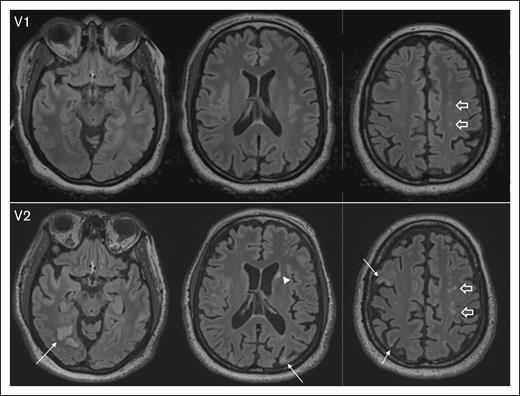

The median ARWMC score significantly increased from 3 (IQR, 0-7) at baseline (visit 1) to 4 (IQR, 1-7) at visit 2 (P = .002), suggesting ongoing cerebrovascular injury despite the absence of acute iTTP episodes. Representative MRI images illustrate the development of new lesions and the enlargement of existing SCI from visit 1 to visit 2 (Figure 2).

Representative images depicting progression of SCI burden between V1 and visit 2 V2, with brain MRI completed 12 months apart. At V1, axial fluid-attenuated inversion recovery (FLAIR) images show several punctate foci of hyperintensity in the centrum semiovale (block arrows). At V2, there is interval development of multifocal chronic cortical infarcts; for example, in the right occipital, right and left parietal lobes, and right middle frontal gyrus (arrows), as well as an ischemic focus in the left caudate head (arrowhead). In addition, multifocal FLAIR hyperintense white matter lesions in the centrum semiovale bilaterally have increased in number and conspicuity (block arrows). V1, visit 1; V2, visit 2.